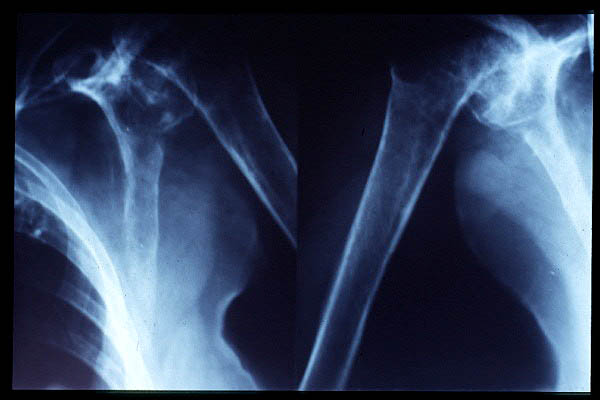

Fractura de húmero, intensa desviación de fragmentos

Fractura de húmero.

Fractura compleja de húmero.